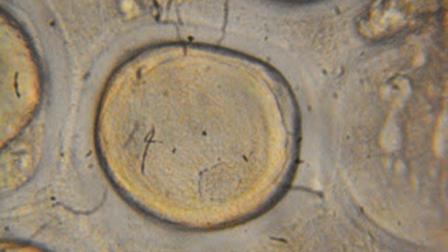

En 1677 el inventor del microscopio, el holandés Antonie van Leeuwenhoek, estudió el semen humano y fue el primero en ver espermatozoides. Supuso que el espermatozoide es una suerte de semilla, al tiempo que el útero femenino sólo le crea un ambiente favorable para su “germinación”.

El holandés Antoni van Leeuwenhoek, estudió el semen humano y fue el primero en ver espermatozoides